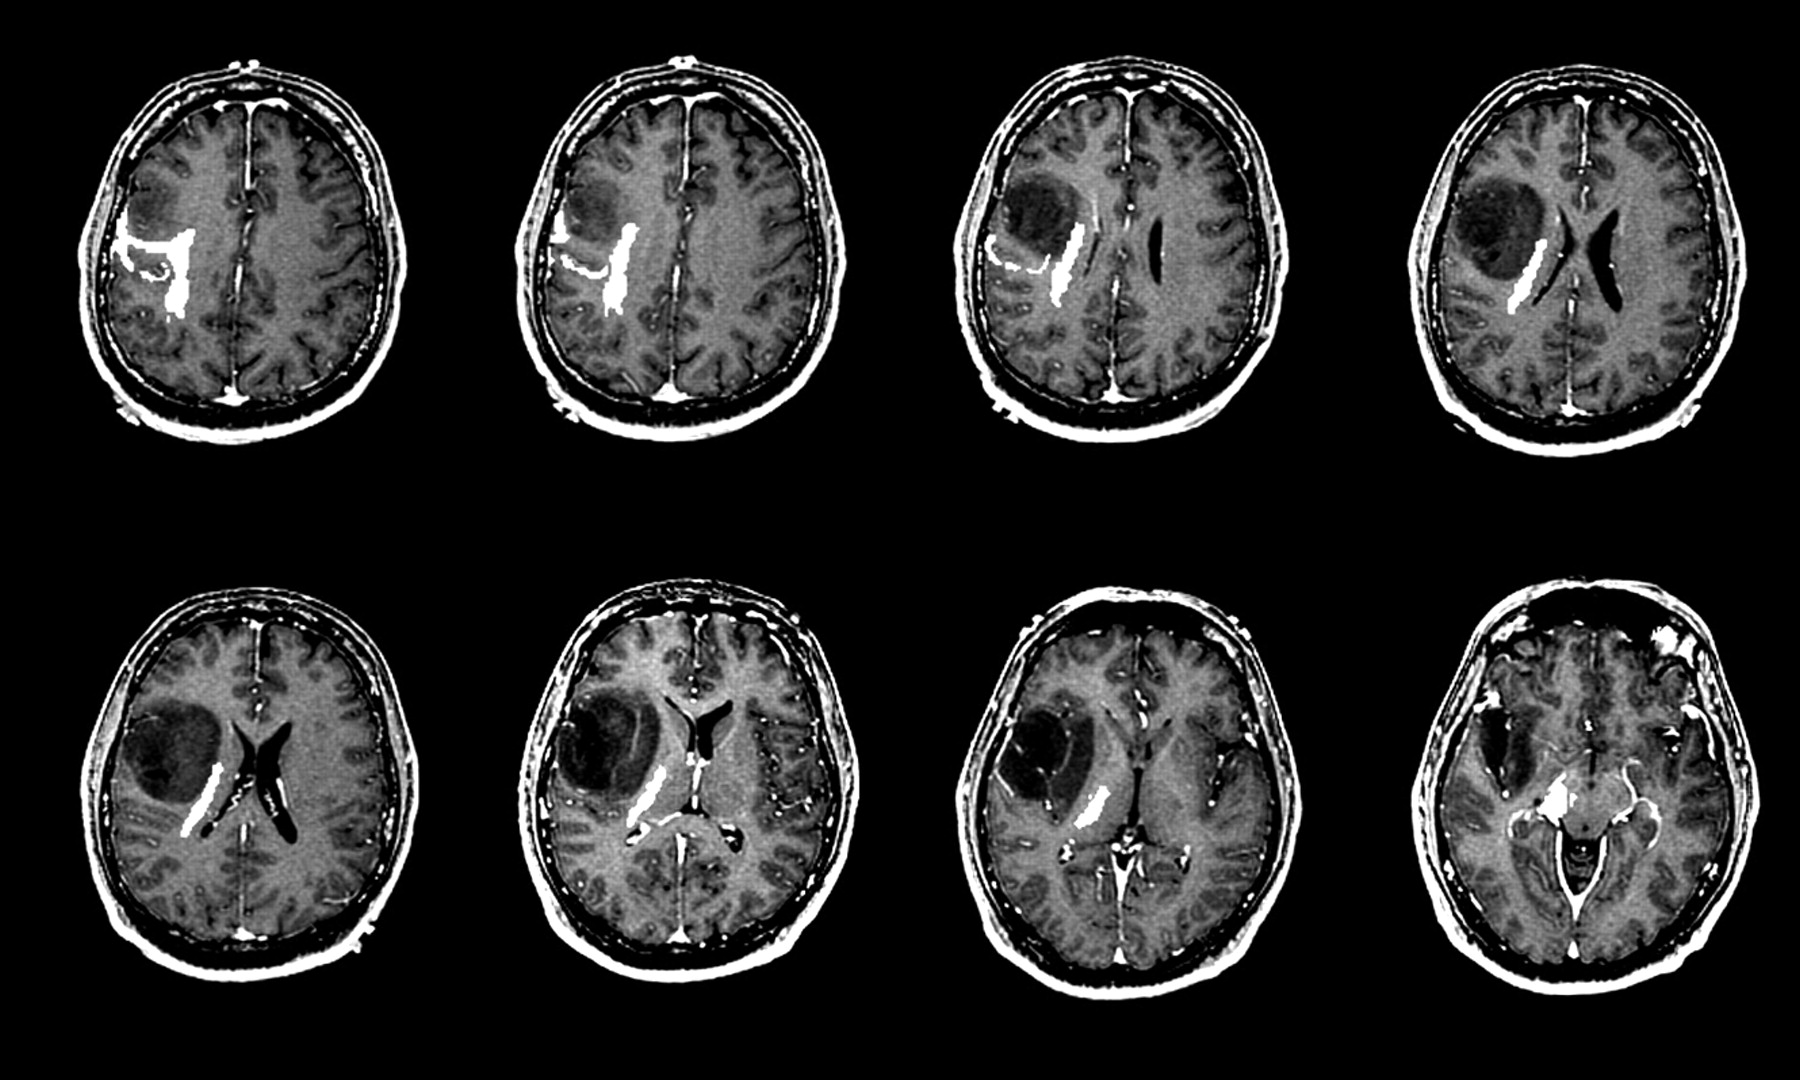

When an uncal herniation brain shift is suspected, time is the absolute priority. Diagnostic imaging is required to confirm the presence and location of the mass effect. A Computed Tomography (CT) scan is the gold standard in an emergency setting because it is fast and widely available. It can reveal:

Midline Shift Indicates significant pressure pushing structures across the center of the brain.

Effacement of Basal Cisterns Suggests the brain tissue is being forced into areas where it does not belong.

Temporal Lobe Mass Identifies the primary cause, such as a bleed (hematoma) or tumor.

• uncal herniation on ct scan